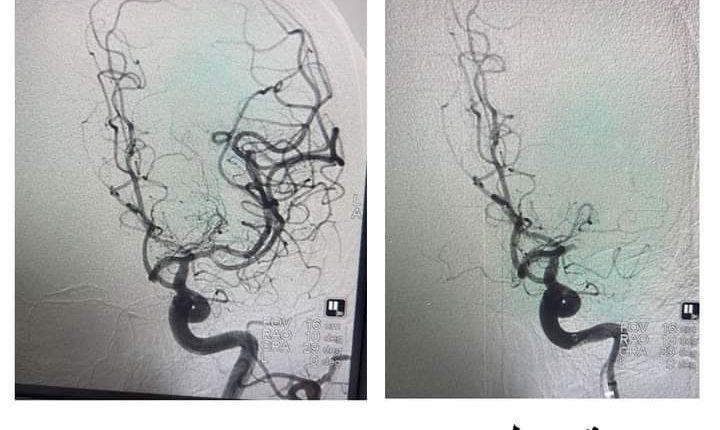

حيث اثرت الجلطة الدماغية على النطق لديها بالاضافة الى ضعف حاد في الجزء الايمن من الجسم، وتم الاتصال مع طوارىء المستشفى التخصصي وحضرت المريضة خلال أقل من ساعة من بدء حدوث الاعراض، وتبين من الصورة الطبقية وجود انسداد كامل في الشريان السباتي الايسر والشريان الأوسط الدماغي وتم تشخيصها بجلطة وتم تفعيل stroke code (رمز الجلطات الدماغية) وبدء الاجراءات بشكل سريع، وتم نقل المريضة الى قسم القسطرة، حيث قام الدكتور حازم حبوب استشاري الاشعة التداخلية ومعالجة الجلطات الدماغية مع الفريق الطبي والتمريضي بإجراء عملية سحب الخثرة خلال مدة زمنية قصيرة جداً (عشرين دقيقة) وضمن بروتوكول الاعتمادية الدولية لوحدة الجلطات الدماغية للمستشفى التخصصي.

وقد تكللت العملية بالنجاح وتعافت المريضة خلال 48 ساعة بشكل تام وعادت لممارسة حياتها الطبيعية، وتقدمت بالشكر الجزيل للفريق الطبي ولإدارة المستشفى التخصصي على سرعة الاجراءات والاستجابة في مثل هذه الحالات.